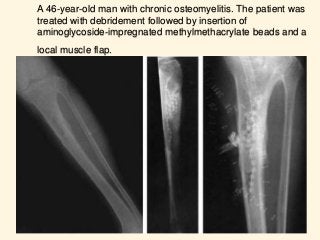

A 46-year-old man with chronic osteomyelitis. The patient was

treated with debridement followed by insertion of

aminoglycoside-impregnated methylmethacrylate beads and a

local muscle flap.

A 46-year-old manwith chronic osteomyelitis. The patient was treated with debridement followed by insertion of aminoglycoside-impregnated methylmethacrylate beads and a local muscle flap.